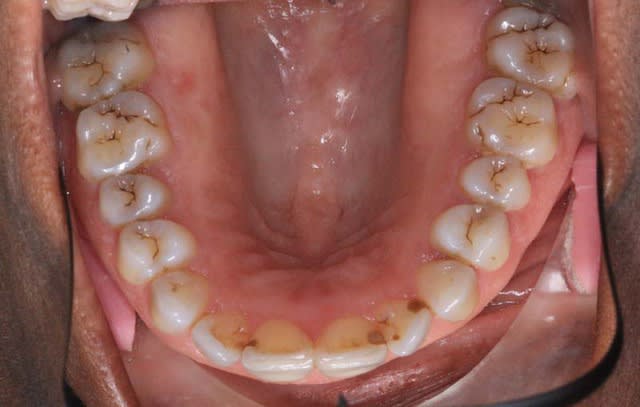

c‘est un cas que j’ai vu ce matin

La patiente (66 ans) se plaint de douleurs au niveau de l’A.T.M.

Pourtant y'a tous les critères de Planas, Md carrée, facettes d'usure, pas de protection canine ( semble-t'il)donc elle devrait pas souffrir, c'est une simulatrice!

P.S.: ce qui est remarquable est qu'il y beaucoup de critères de Planas

Occlusion imparfaite : presque ne bord à bord au niveau incisal

12 : usure ++

perte des protections canines

pas de mylolyse

peu d'usure indiquant un bruxisme horizontal

pas de 8 max sur les photos mais présence de 8 mandibulaires

> interférence des 48/38 avec les 17/27 ?

Au niveau dentodentaire la situation si elle n'est pas idéale n'est pas catastrophique.